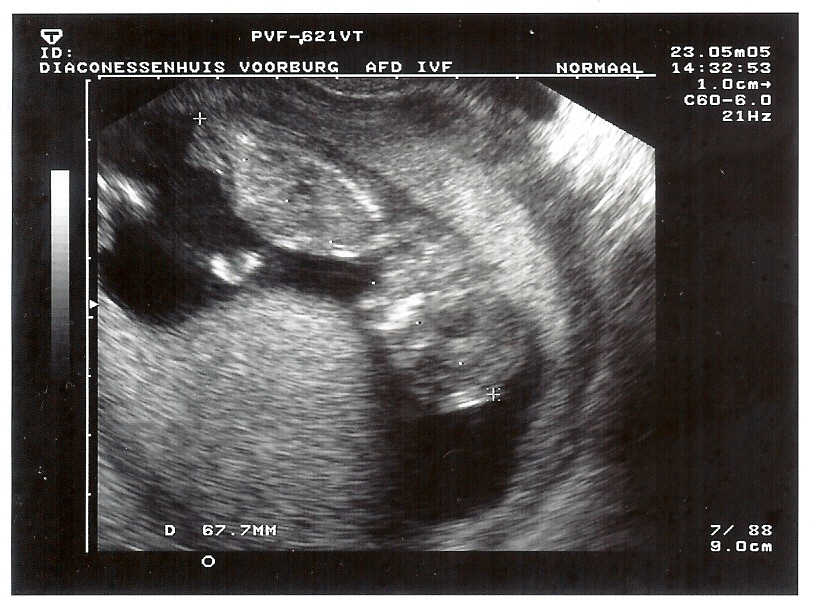

23-5-2005 Danique 12 weken, 4 dagen, 67.7mm